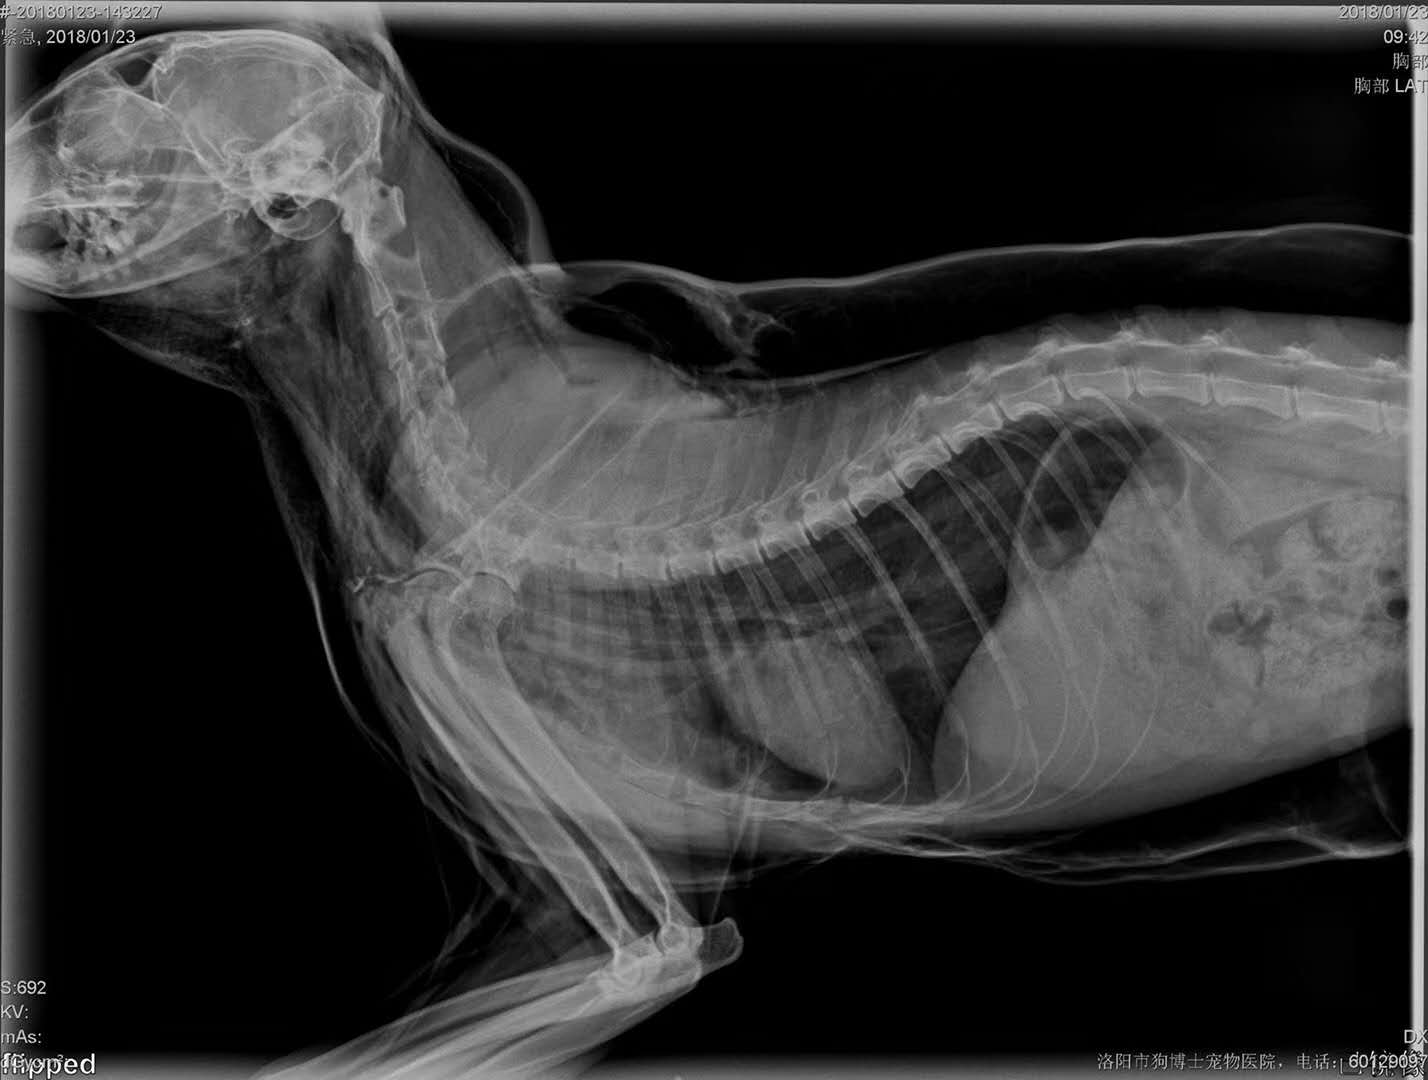

轉(zhuǎn)院全身氣腫病例治愈出院:暹羅貓,發(fā)財(cái),近期在其他醫(yī)院做的絕育手術(shù),術(shù)后出現(xiàn)全身氣腫(第2,第3張照片為原醫(yī)院拍攝),轉(zhuǎn)賬至我院,經(jīng)我院檢查發(fā)現(xiàn),在貓咪氣管入胸段,約有5.6mm大小孔洞,氣體延此孔泄露,并移行到頸部背測,接入皮下疏松結(jié)締組織,進(jìn)一步擴(kuò)散至全身。推測可能與絕育手術(shù)呼吸麻醉時(shí)氣管插管不當(dāng)有關(guān)。我院采取壓迫保守療法,住院10天,痊愈出院。PS:寵物主人選擇醫(yī)院時(shí),一定要慎重,就診時(shí)關(guān)鍵是大夫水平,其他是次要因素。